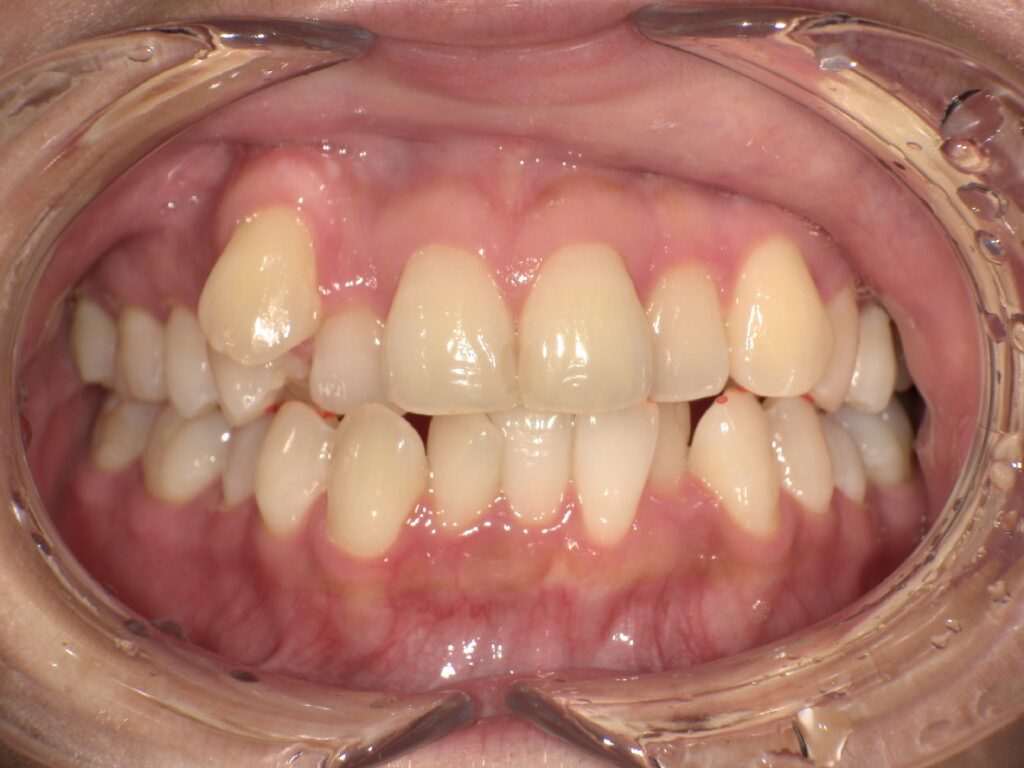

上顎の前歯が大きく突出しています

明らかに前歯の突出感が改善し、患者様はこの時点でとても喜ばれていました